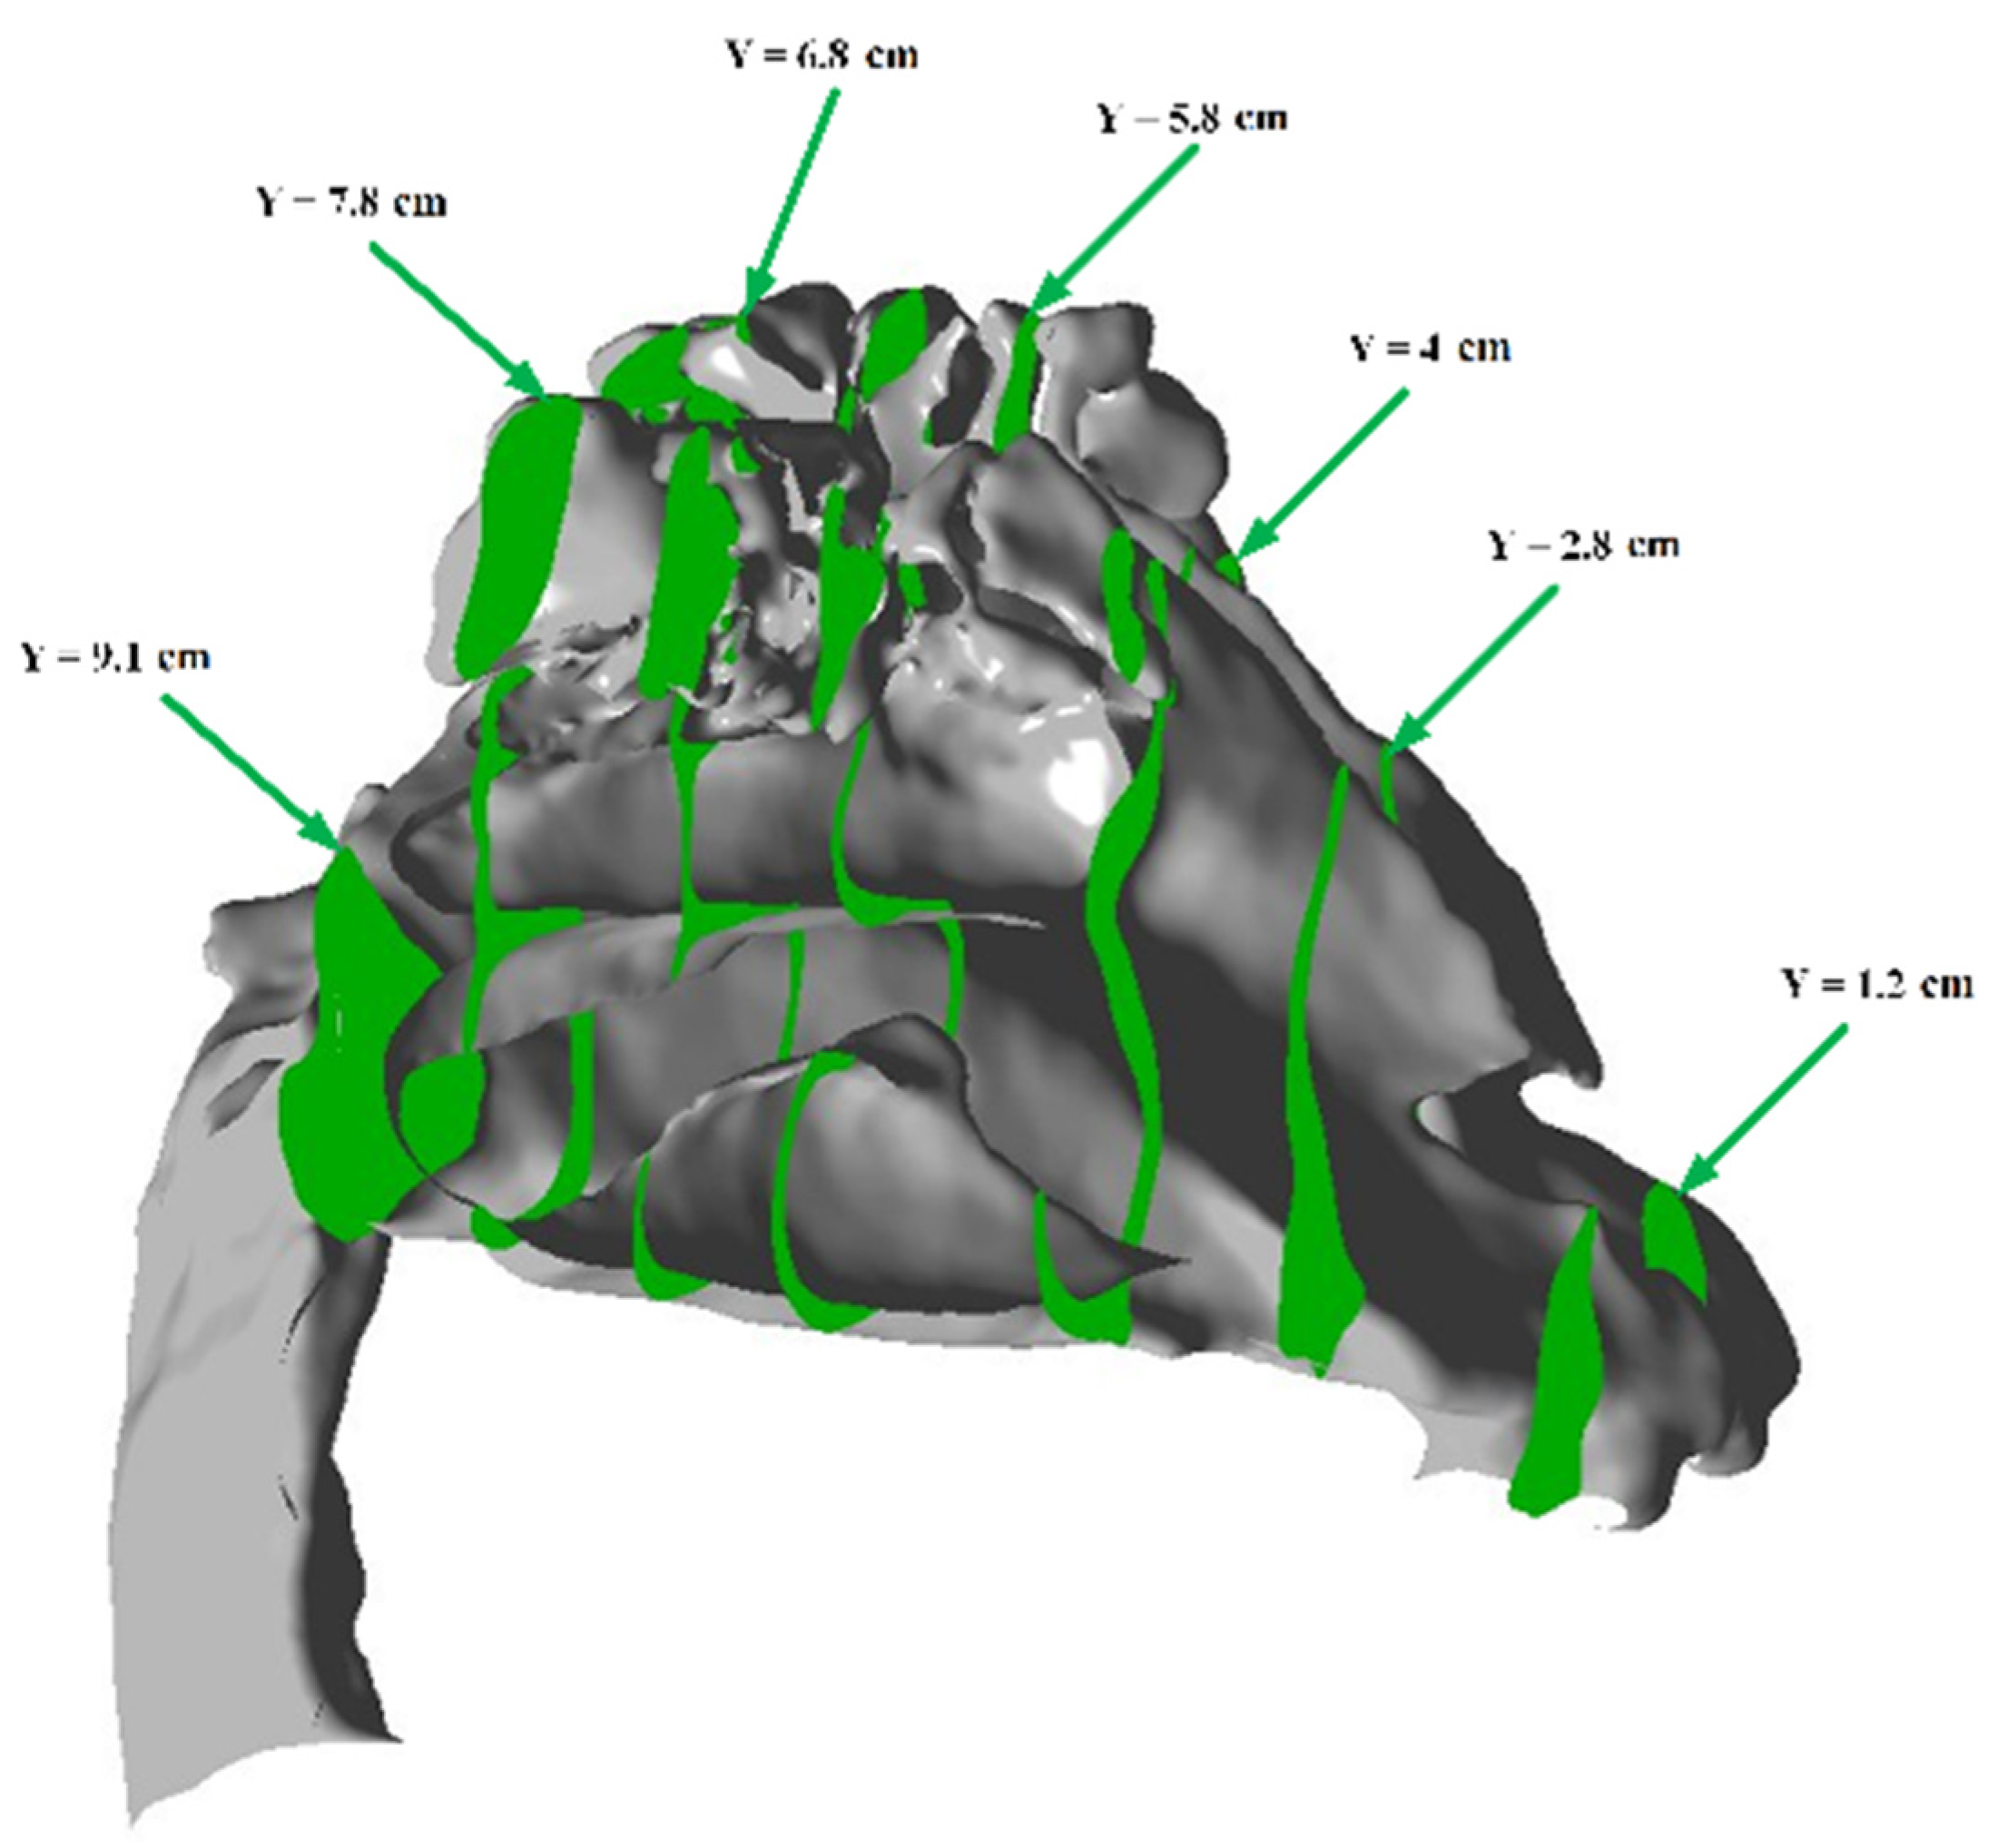

In this work, the average value of the flow rate was used as a parameter for adaptation. To determine the average speed and adjust the computational domain based on the geometry, auxiliary parallel planes were created. For example, in the case of the nasal cavity, sections were created in the OY plane, as shown in green in Figure 12.

In order to adapt the computational domain, a criterion similar to that of the nasal cavity, namely, the average velocity, was used. Due to the particular geometry of the lungs, parallel sections were created in the OZ plane, as shown schematically in Figure 16.

Figure 12. Auxiliary cutting planes perpendicular to the Y axis for adapting the computational mesh of the nasal cavity.

Figure 16. Auxiliary cutting planes perpendicular to the Z axis for adapting the computational mesh of the bronchopulmonary trunk.